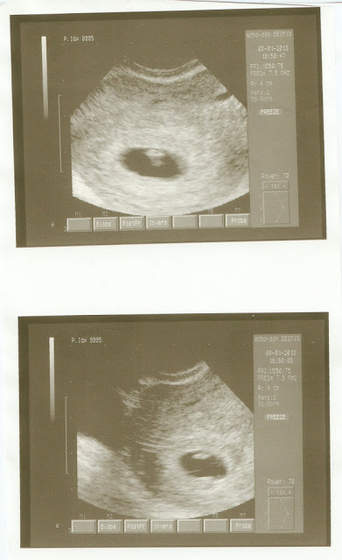

No więc we wtorek poszłam do zaufanego ginka mojej przyjaciółki (niestety płacąc już za wizytę), ale wizyta warta każdych pieniędzy, bo łzy radości gdy się widzi fasolkę na USG i te emocje... niesamowite

Dziś zrobiłam wszystkie testy krwi i moczu i większości mam już wyniki. Beta HCG blisko 25tys